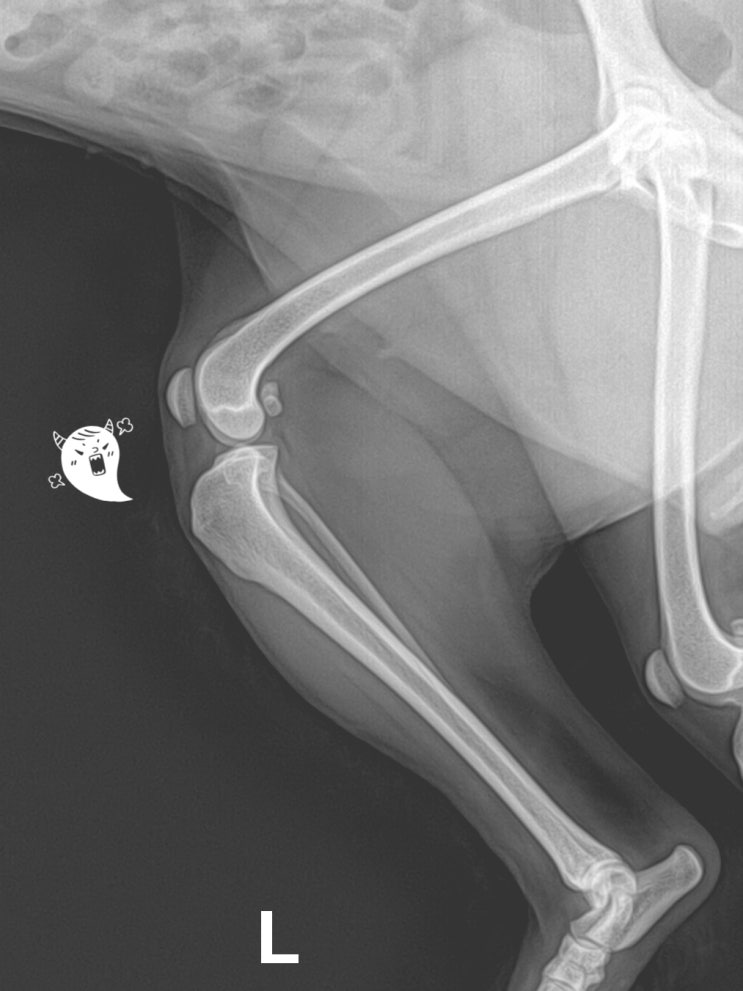

1살 포메라니안 강아지 양측 슬개골 탈구 수술 후기 / 반려견 양측 슬개골탈구 수술 후 주의점 / 어린 강아지 무릎 수술 꼭 해야 할까요? / 애완견 슬개골 탈구 전문 동물병원

안녕하세요~ 굿파파 수의사입니다. 오늘부터 따뜻한 봄기운이 느껴지네요~ 행복한 미소 가득한 하루 보내세...

7살 말티즈 강아지 슬개골 탈구 수술 후기 / 반려견 슬개골탈구 수술 후 주의 사항 / 애완견 슬개골 탈구 가장 좋은 수술 방법은? / 강아지 관절 주사 전문 동물병원

안녕하세요~ 굿파파 수의사입니다. 개나리가 예쁘게 피었네요~ 행복한 봄 ~ 즐거운 하루 보내세요~ 오늘의 ...

4살 말티즈 강아지 슬개골 탈구 수술 후기 / 반려견 슬개골탈구 수술 중 가장 방법은? / 애완견 뒷다리를 들고 걷는 원인, 이유 / 애견 슬개골탈구 수술 가격, 비용 안내

안녕하세요~ 굿파파 수의사입니다. 비가 오는 토요일이네요~ 벚꽃이 만개하고 있네요~^^* 비가 멈추면 벚꽃...

1살 푸들 강아지 슬개골 탈구 수술 후기 / 반려견 슬개골 외측 인대 파열 수술 가격, 비용 / 강아지 뒷다리를 들고 걷는 이유 / 애완견 무릎 수술 전문 24시 동물병원

안녕하세요~ 굿파파 수의사입니다. 내일은 식목일이네요^^* 주말에 가족과 함께 나무 심는 시간을 갖는 건 ...